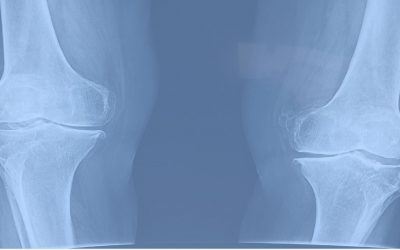

ข้อเข่าเสื่อม โรคยอดฮิตของผู้สูงอายุ ด้วยสังคมไทยกำลังก้าวสู่ “สังคมผู้สูงอายุ – Aging Society” อย่างเต็มรูปแบบ มีตัวเลขจากสถาบันวิจัยประชากรและสังคม พ.ศ.2548